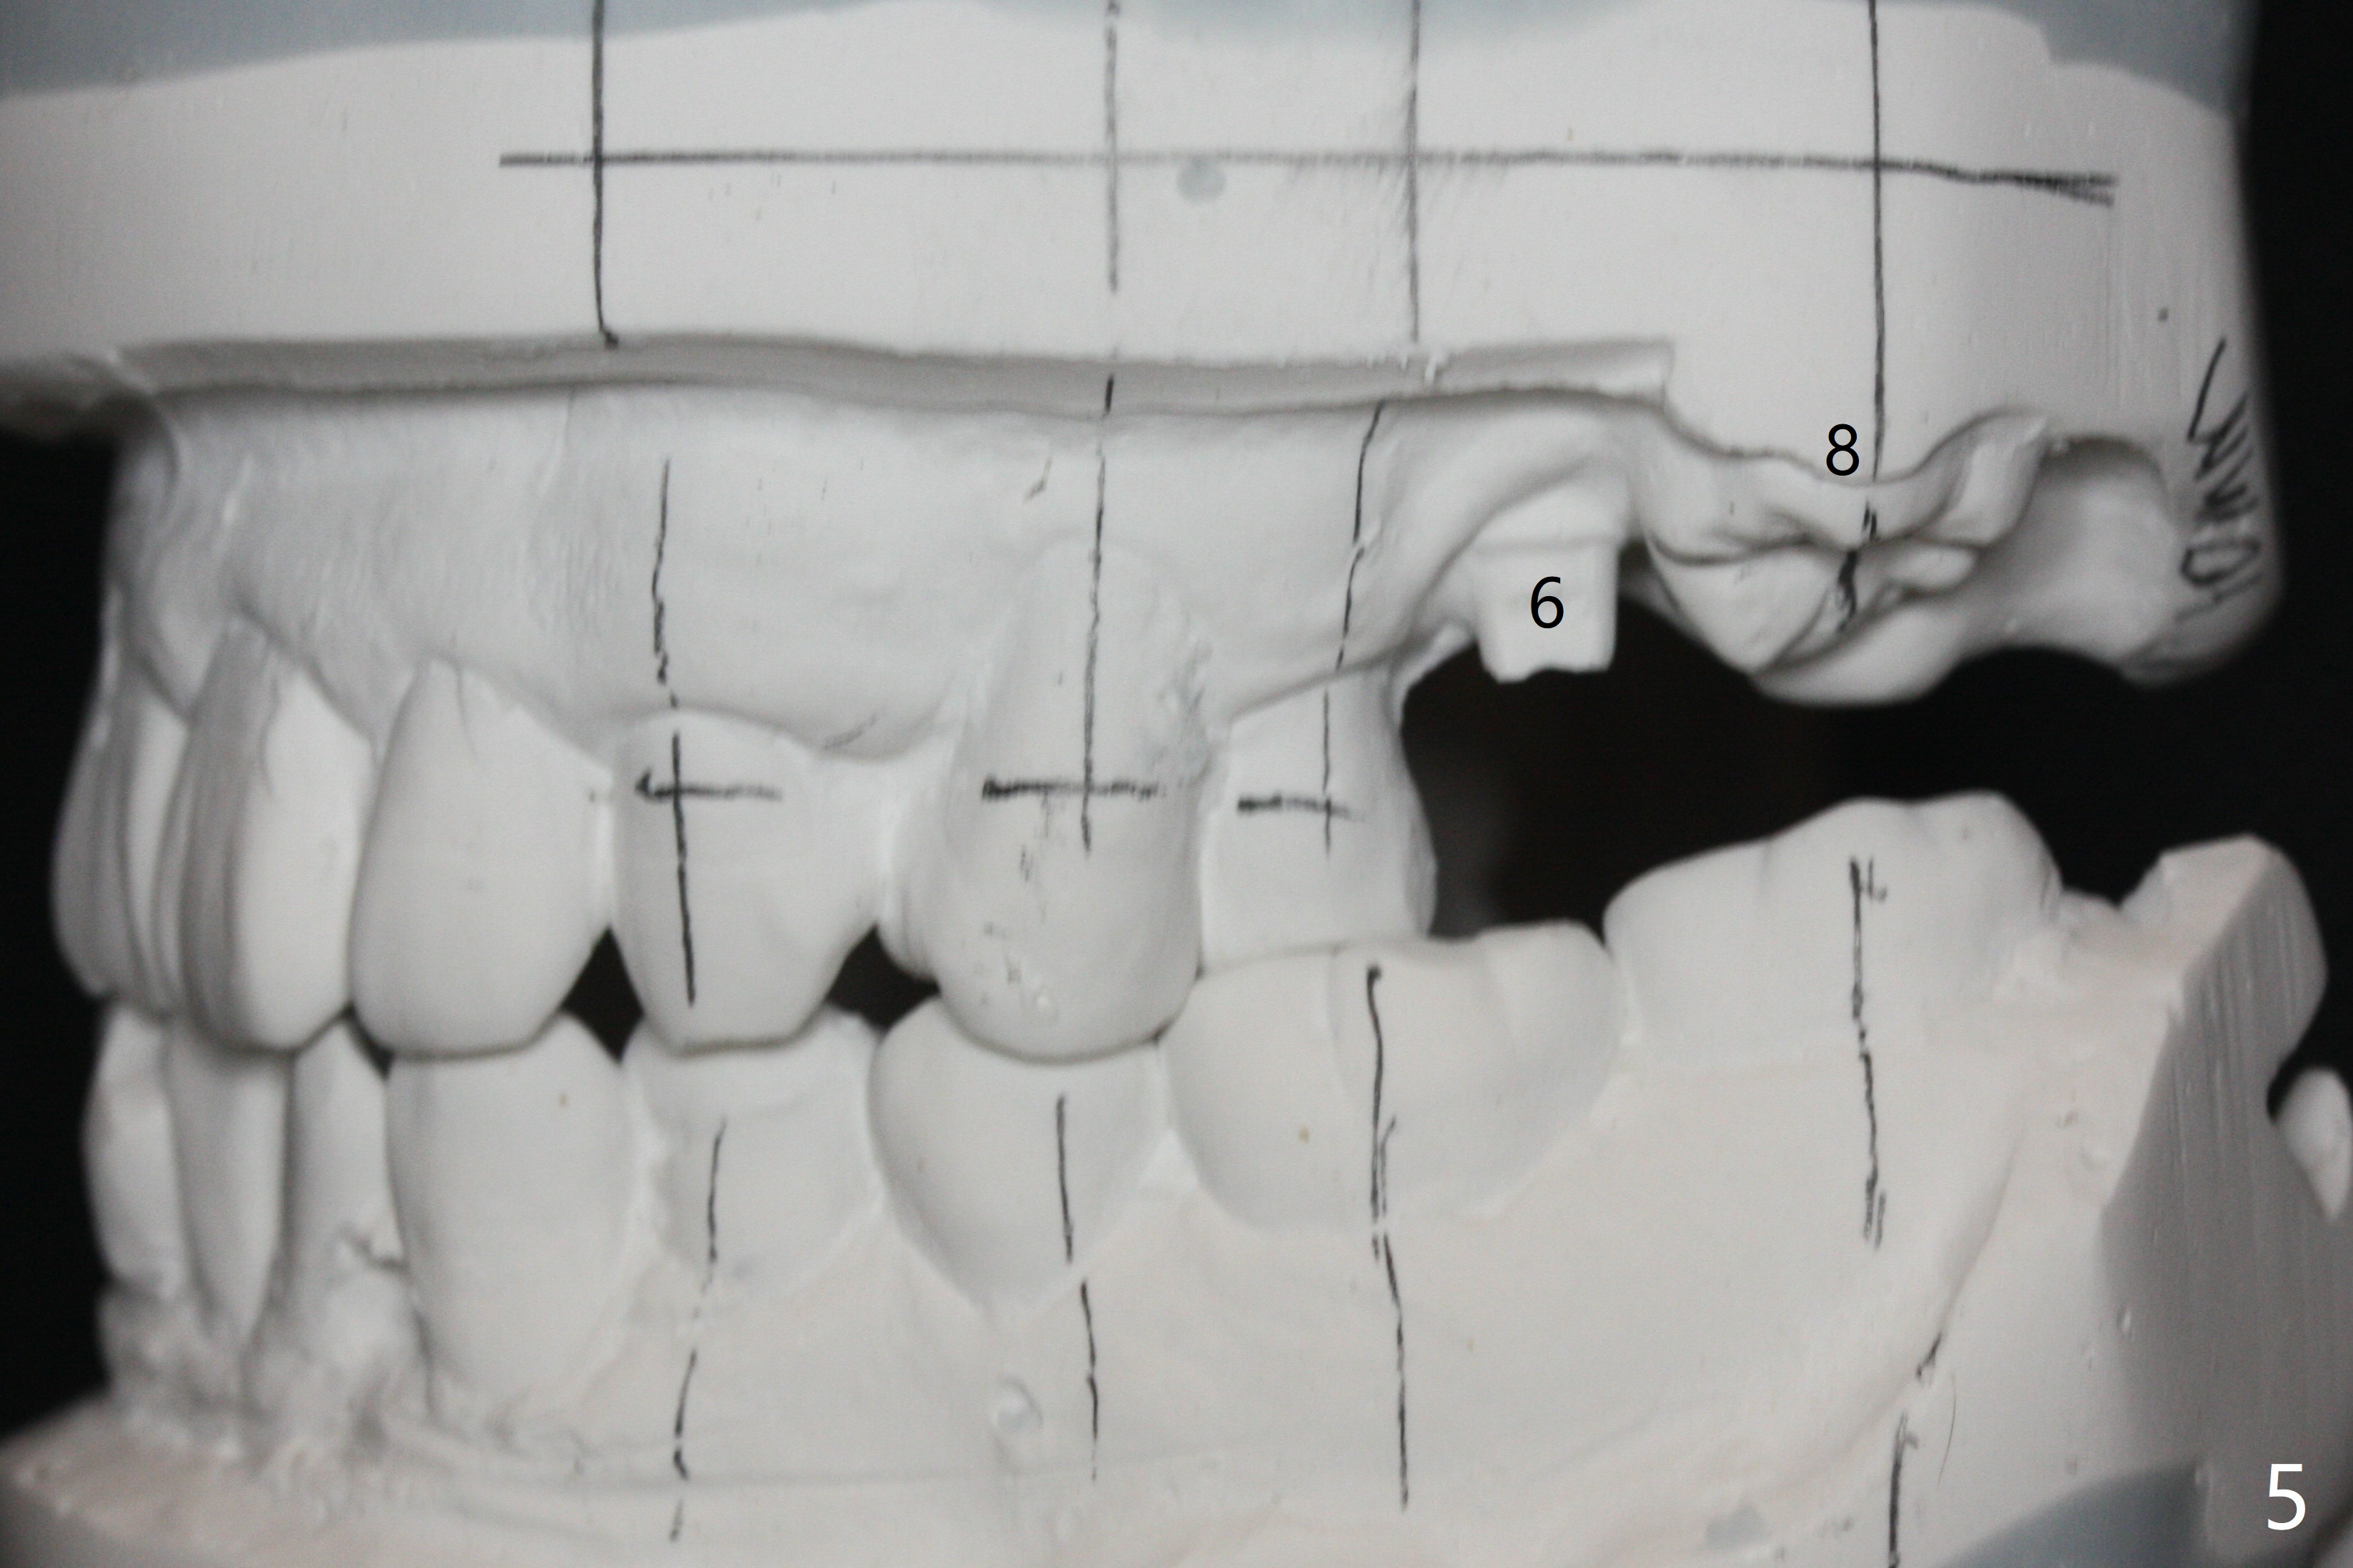

A 45-year-old man with normal facial profile (Fig.1-4) and malocclusion confined to UL quadrant (Fig.5-6) agrees with comprehensive orthodontic treatment. The implant threads at UL6 remain exposed 2 years 4 months postop. Thread exposure should disappears by distalizing UL5 and extruding UL8. Although upper wire sequence should be able to the limited malocclusion, extrusion of UL8 may use the lower arch as an anchor (elastic once a rectangular wire is installed, Fig.7,8).